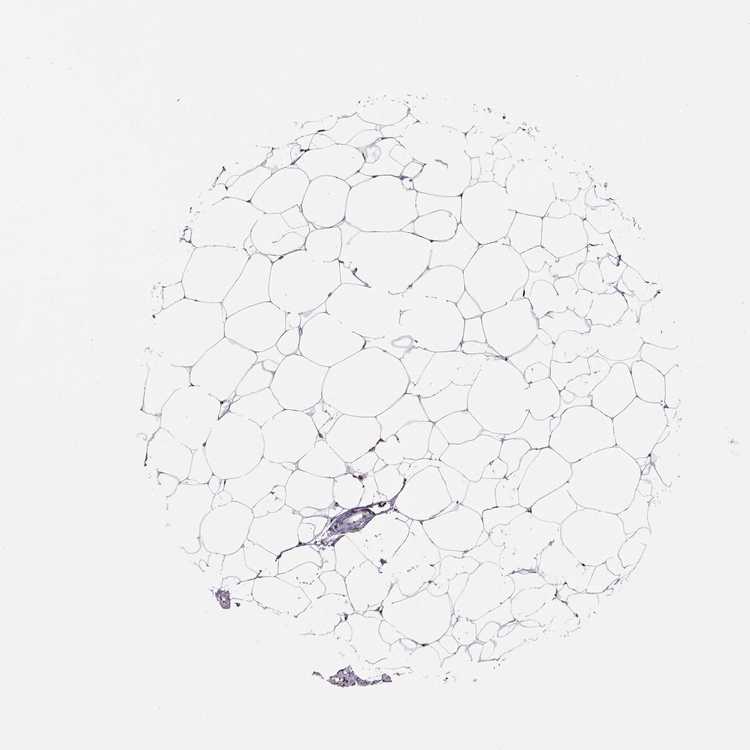

BREAST - Antibody stainingi

Antibody staining in the annotated cell types in the current human tissue is reported as not detected, low, medium, or high, based on conventional immunohistochemistry profiling in selected tissues. This score is based on the combination of the staining intensity and fraction of stained cells.

Each image is clickable and will lead to virtual microscopy that enables deeper exploration of all samples and also displays staining intensity scores, fraction scores and subcellular localization as well as patient and tissue information for each sample.

Antibody HPA069985Antibody CAB005883Antibody CAB078687Antibody CAB080398

Adipocytes HighNot detectedNot detectedHigh

Glandular cells HighHighNot detectedMedium

Myoepithelial cells MediumHighNot detectedMedium